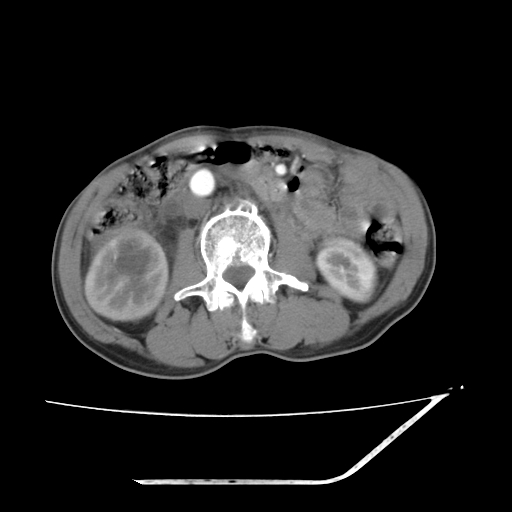

增强

考虑右肾盂癌,肾动脉受侵,右肾功能减退,右肾盂输尿管积水,管壁增厚,考虑种植转移,应该把下面扫完的

支持右侧肾盂癌伴肾静脉瘤栓形成可能性大,右肾结石.肝右叶后段低密度影,不除外转移.

考虑右肾盂癌,肾动脉受侵,右肾功能减退,右肾盂输尿管积水,管壁增厚,考虑种植转移  支持

右肾盂旁ca并肾静脉瘤栓形成/肾功能降低。

右肾结石。

右肾盂癌,肾动脉受侵,右肾盂输尿管积水,管壁增厚,考虑种植转移

支持 右侧肾盂癌伴肾静脉瘤栓形成可能性大,右肾结石;肝右叶后段低密度影,不除外转移。

1.右侧肾盂癌伴肾盂积水。

2.肾脏功能减退,原因有:(1)肾动脉受侵。(2)肾静脉受侵(3)肾积水,等。本例,肾动脉显影较好,但受压明显;肾静脉无明显显示,受压或静脉癌栓,下腔静脉腔内未见明显充盈缺损。

3.右侧上段输尿管扩张,原因:(1)积水所致;(2)种植。